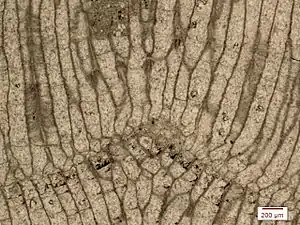

Histology,[help 1] also known as microscopic anatomy or microanatomy,[1] is the branch of biology that studies the microscopic anatomy of biological tissues.[2][3][4][5] Histology is the microscopic counterpart to gross anatomy, which looks at larger structures visible without a microscope.[5][6] Although one may divide microscopic anatomy into organology, the study of organs, histology, the study of tissues, and cytology, the study of cells, modern usage places all of these topics under the field of histology.[5] In medicine, histopathology is the branch of histology that includes the microscopic identification and study of diseased tissue.[5][6] In the field of paleontology, the term paleohistology refers to the histology of fossil organisms.[7][8]

For light microscopy, a knife mounted in a microtome is used to cut tissue sections (typically between 5-15 micrometers thick) which are mounted on a glass microscope slide.[9] For transmission electron microscopy (TEM), a diamond or glass knife mounted in an ultramicrotome is used to cut between 50 and 150 nanometer thick tissue sections.[9]

Staining

Biological tissue has little inherent contrast in either the light or electron microscope.[17] Staining is employed to give both contrast to the tissue as well as highlighting particular features of interest. When the stain is used to target a specific chemical component of the tissue (and not the general structure), the term histochemistry is used.[9]

Light microscopy

Hematoxylin and eosin (H&E stain) is one of the most commonly used stains in histology to show the general structure of the tissue.[9][18] Hematoxylin stains cell nuclei blue; eosin, an acidic dye, stains the cytoplasm and other tissues in different stains of pink.[9][12]